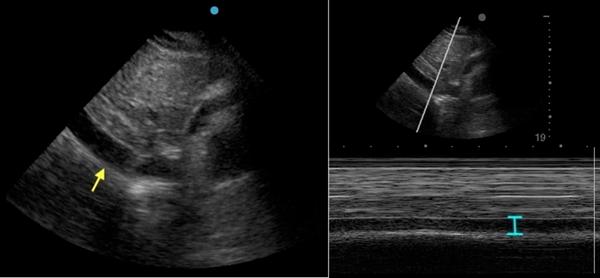

床旁即时超声(POCUS)检查显示中度心包积液以及右心房(图2)和右心室(图3)舒张期塌陷,下腔静脉(IVC)直径增加不随呼吸期变化(图4)。

(图4 POCUS检查显示下腔静脉直径增加)